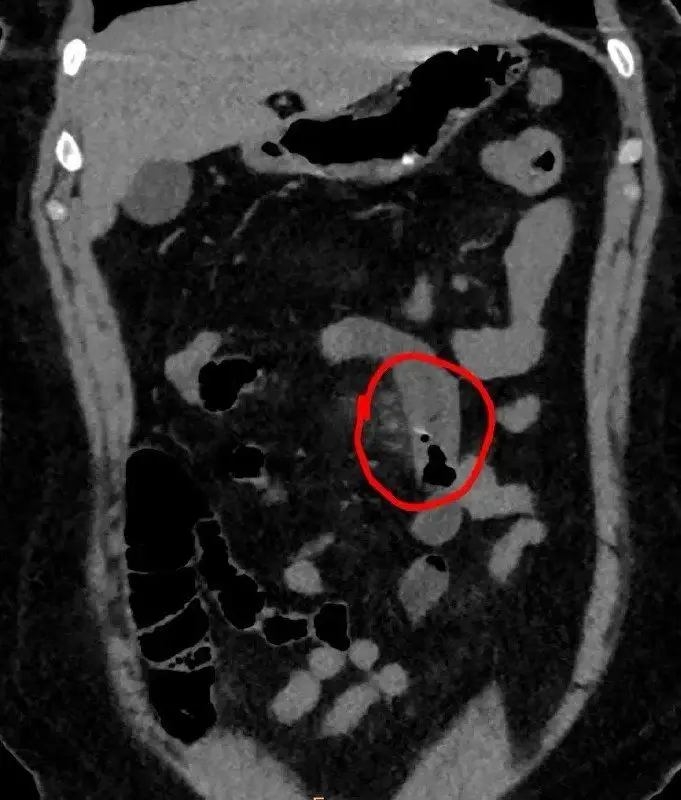

Крошечная кость застряла в кишечнике женщины, ее достали методом лапароскопии.

«На компьютерной томографии рентгенолог сумел увидеть в тонкой кишке инородное тело — крошечную рыбью кость. Хирурги приняли верное решение: лапароскопически, через минимальный разрез над костью инородное тело было аккуратно извлечено, а стенка кишки ушита. Пациентке удалось избежать перфорации, развития перитонита и обширной полостной операции», — рассказала Лилия Самошина.